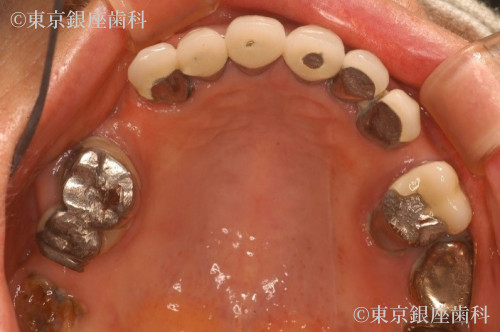

初診時のお口の状態は、複数の奥歯が抜けていて、残っている奥歯も歯周病や、虫歯・根尖病巣により予後が不良(長期的に歯の保存が望めない)な状態でありました。

また、奥歯で物を噛めないため前歯で咀嚼を長期にわたり行うことで、前歯への力の負担が強くなり歯の根がヒビが入ったり、折れてしまっている状態でした。

奥歯を何らかの原因により失ってしまい、長期間にわたり咀嚼力の負担が前歯にかかると前歯も歯にひびが入ったり折れてしまい予後が不良となり、また骨の吸収も生じることがあります。

術前の口腔内の診査で残っている歯の状態の確認をしてお口全体の確認をする事が重要となります。